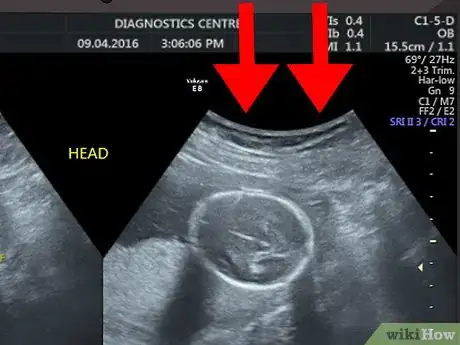

Start from the top of the image. The top of the screen or printed image is where the ultrasound probe was placed. In other words, the image you see shows what the organ or tissues look like from the side rather than from the top.[2]

• For example, if you are having an ultrasound of your uterus, then what you see at the top of the screen or printed ultrasound would be the outline of the tissues above your uterus. As you look further down the screen, you will see deeper tissues, such as the lining of your uterus, the inside of your uterus, and the back of your uterus.